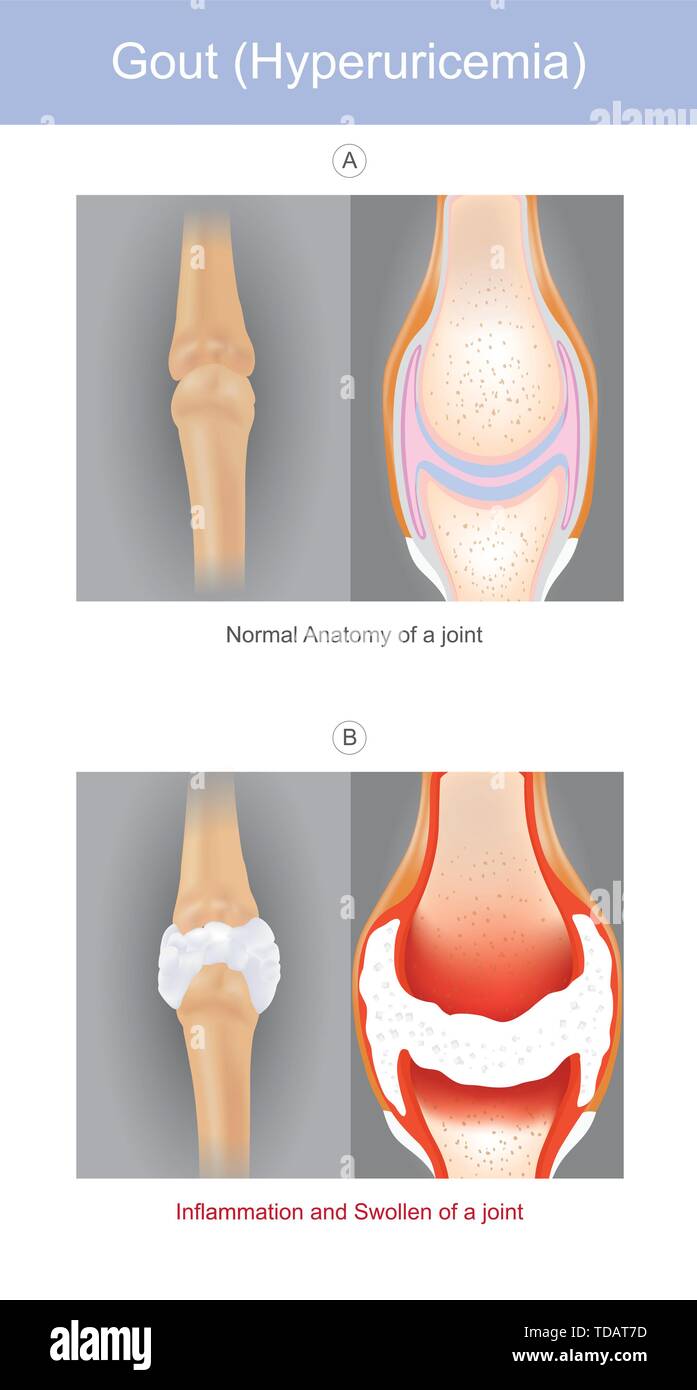

La illustrata una forma di artrite che può essere molto dolorosa è provocato dalla presenza di urato di sodio cristalli in articolazioni le dita mani o dita. Illustrazione Vettorialehttps://www.alamy.it/image-license-details/?v=1https://www.alamy.it/la-illustrata-una-forma-di-artrite-che-puo-essere-molto-dolorosa-e-provocato-dalla-presenza-di-urato-di-sodio-cristalli-in-articolazioni-le-dita-mani-o-dita-image249174225.html

La illustrata una forma di artrite che può essere molto dolorosa è provocato dalla presenza di urato di sodio cristalli in articolazioni le dita mani o dita. Illustrazione Vettorialehttps://www.alamy.it/image-license-details/?v=1https://www.alamy.it/la-illustrata-una-forma-di-artrite-che-puo-essere-molto-dolorosa-e-provocato-dalla-presenza-di-urato-di-sodio-cristalli-in-articolazioni-le-dita-mani-o-dita-image249174225.htmlRFTDAT7D–La illustrata una forma di artrite che può essere molto dolorosa è provocato dalla presenza di urato di sodio cristalli in articolazioni le dita mani o dita.